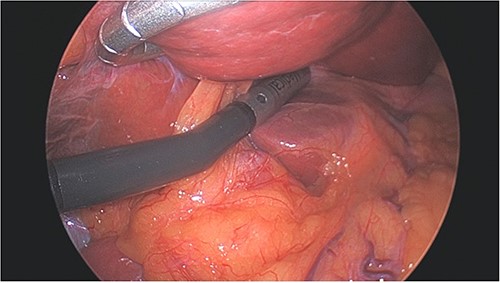

All cases were performed under general anesthesia. Patients were positioned supine, with a 5 mm port placed at the umbilicus and a 12 mm port placed in right flank to allow for ultrasound of liver (Fig. 1). Additional 5 mm ports are positioned as needed for mobilization/retraction of the liver. Using ultrasound guidance (Flex Focus 800, BK Ultrasound), lesions identified on preoperative MRI were identified intraoperatively. Caudate lesions were accessed by elevating the left lobe of the liver (Fig. 2). In some cases, the porta hepatis was encircled with umbilical tape and retracted away from the ablation site. Ablations were carried out with percutaneous introduction of one or two microwave ablation probe(s) (2.45 GHz, PR15XT probes, NeuWave Microwave Ablation System, Ethicon). Ablations of the caudate lobe were performed either alone or in conjunction with ablation of lesions in other hepatic segments. One ablation was performed in combination with resection of the primary tumor, which was of colonic origin.

Patient positioned in reverse Trendelenburg to facilitate exposure of upper abdomen. Port placement: 12 mm port in right upper quadrant to facilitate laparoscopic ultrasound of liver, other 5 mm ports placed as needed for mobilization of liver. Laparoscopic image above patient demonstrates left lobe of liver elevated with retractor, laparoscopic ultrasound probe evaluating left lobe of the liver, and burned area visible in caudate lobe below.

Left lobe of liver elevated with flexible liver retractor, facilitating laparoscopic ultrasound evaluation of caudate lobe.